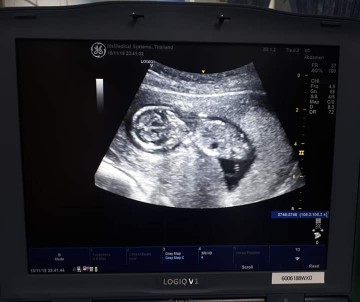

12wค่ะ 13wไม่ได้ซาวค่ะ